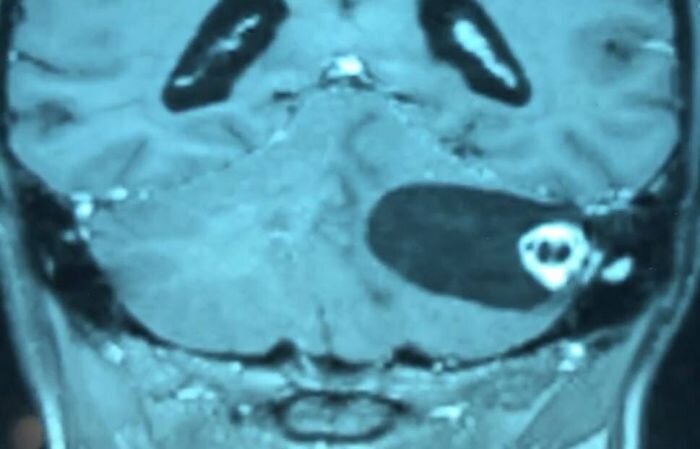

Metastatic lesions of the brain